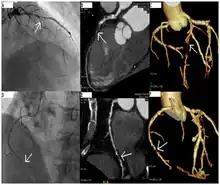

CT angiography can act as a less invasive alternative to Catheter angiography. Instead of a catheter being inserted into a vein or artery, CT angiography involves only the injection of a CT-visible dye into the arm or hand via an IV line. CT angiography lowers the risk of arterial perforation and catheter site infection. It provides 3D images that can be studied on computer, and also allows measurement of heart ventricle size. Infarct area and arterial calcium can also be observed (however those require a somewhat higher radiation exposure). That said, one advantage retained by Catheter angiography is the ability of the physician to perform procedure such as balloon angioplasty or insertion of a stent to improve blood flow to the artery.[7]